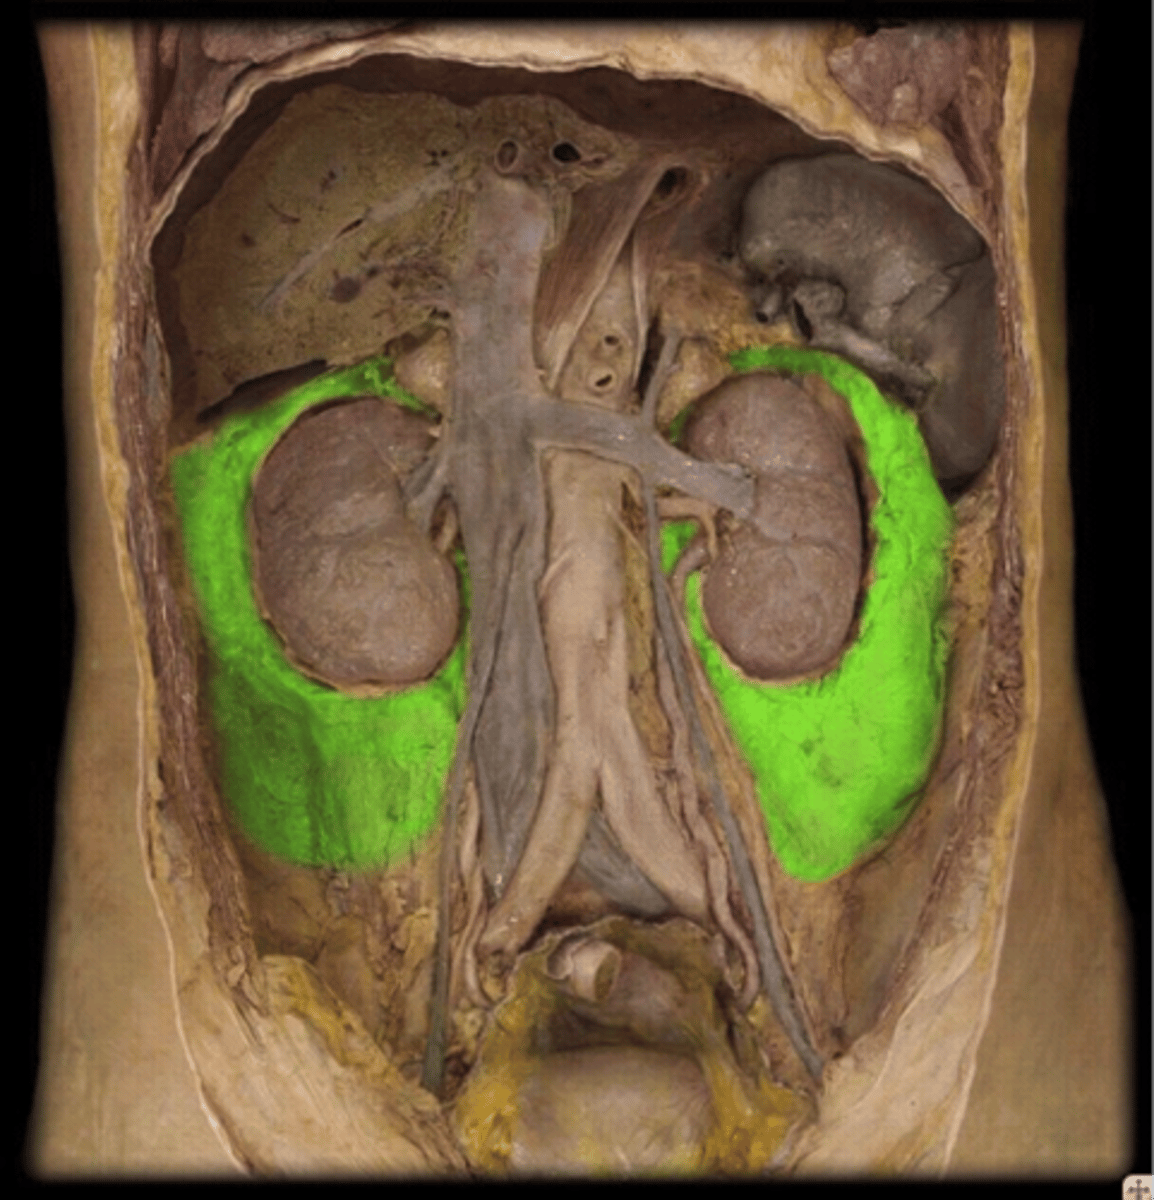

pararenal fat

perirenal fat

hilum (kidney)

left renal vein